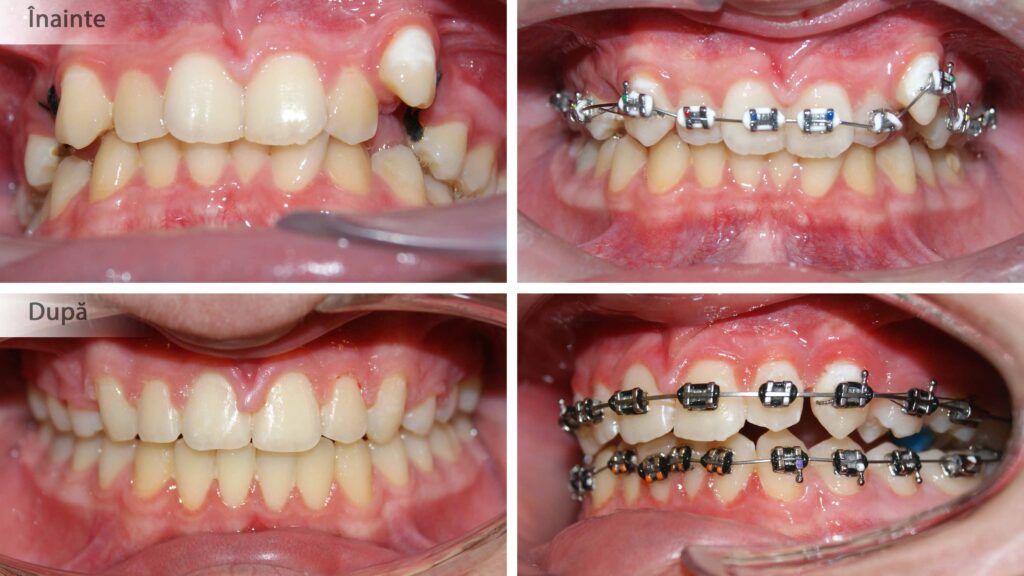

Aparatele ortodontice se aplică doar pe dinții curățați în prealabil. Cariile și resturile radiculare irecuperabile trebuie asanate după cum se vede aici